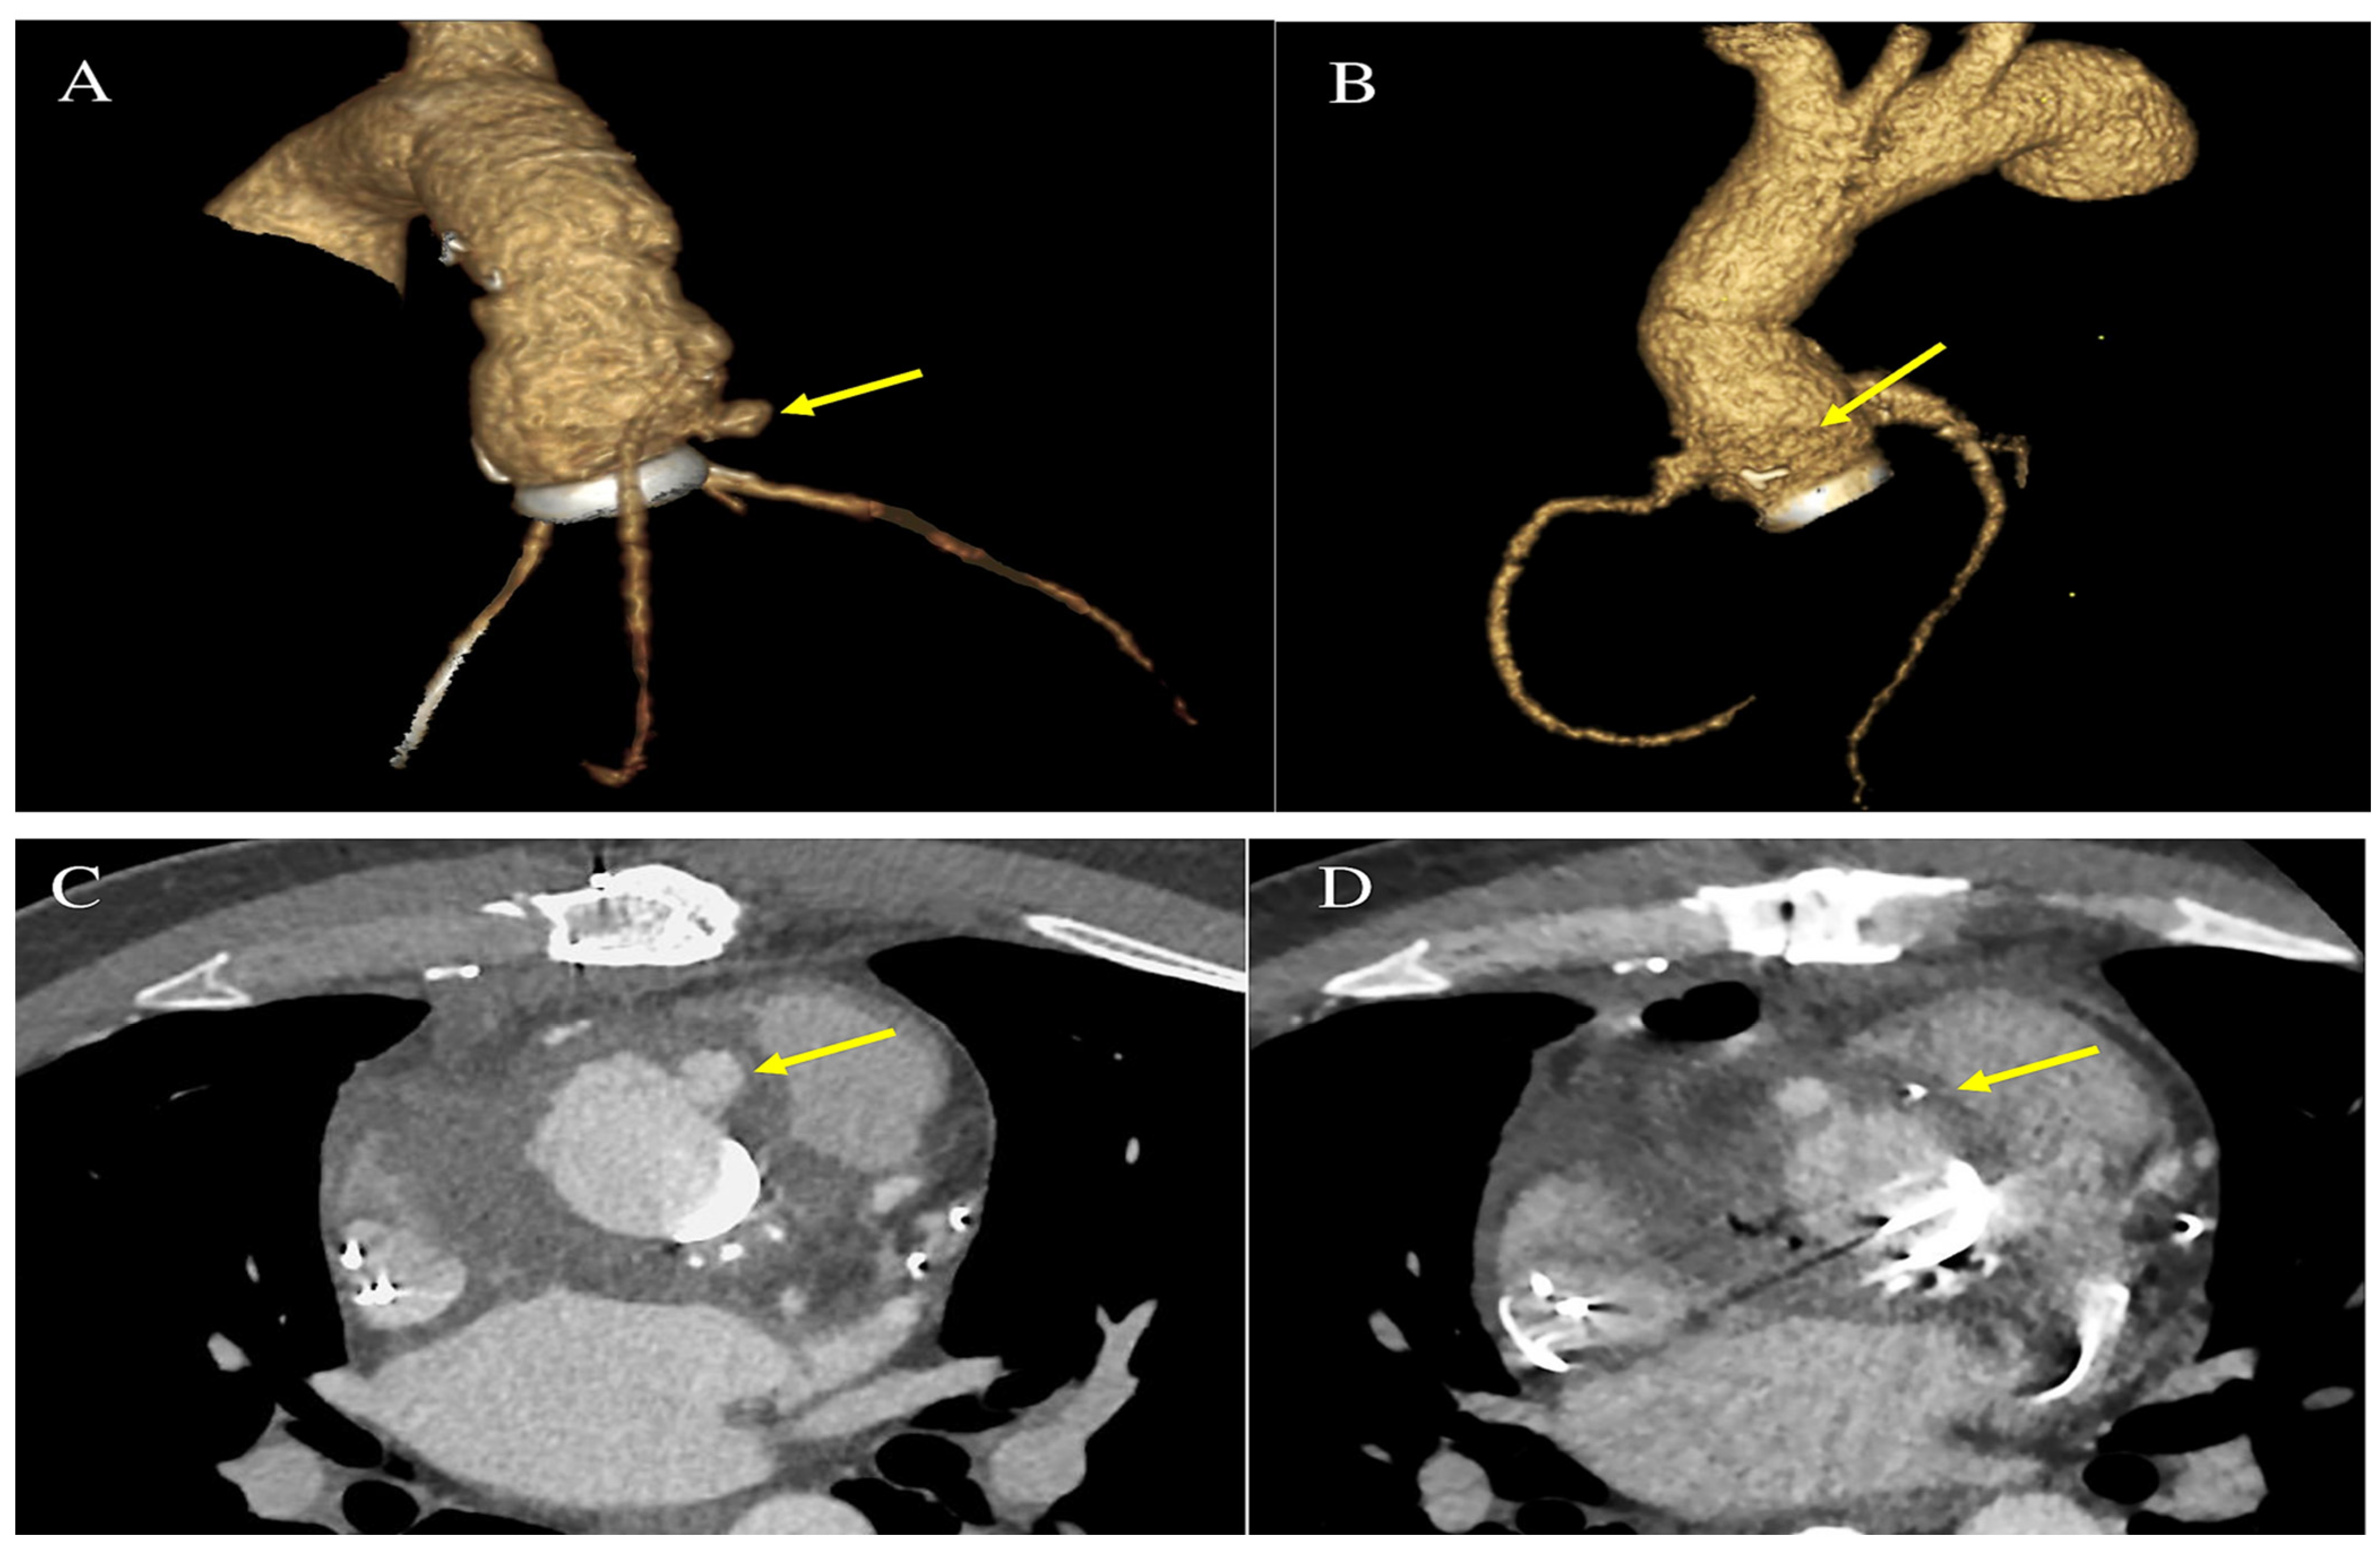

- Khalique, O.K.; Veillet-Chowdhury, M.; Choi, A.D.; Feuchtner, G.; Lopez-Mattei, J. Cardiac computed tomography in the contemporary evaluation of infective endocarditis. J. Cardiovasc. Comput. Tomogr. 2021, 15, 304–312. [Google Scholar] [CrossRef]

- Oliveira, M.; Guittet, L.; Hamon, M.; Hamon, M. Comparative value of cardiac CT and transesophageal echocardiography in infective endocarditis: A systematic review and meta-analysis. Radiol. Cardiothorac. Imaging 2020, 2, e190189. [Google Scholar] [CrossRef]